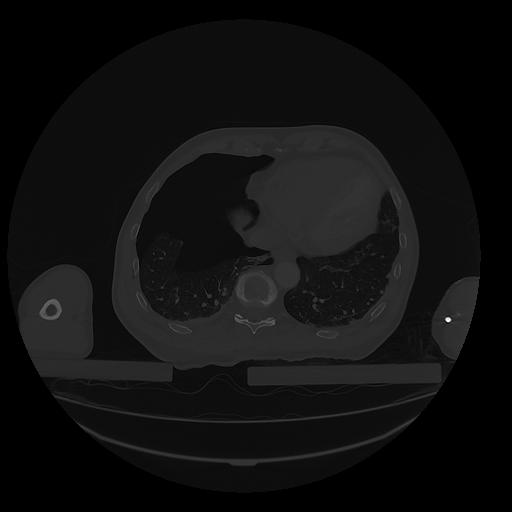

31 PULMON,CE,Vol,1.0,PULMON,,